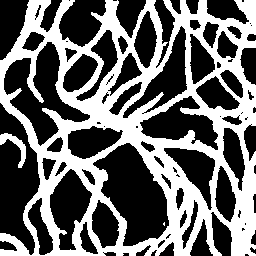

Semantic segmentation of blood vessels is an important task in medical image analysis, but its progress is often hindered by the scarcity of large annotated datasets and the poor generalization of models across different imaging modalities. A key aspect is the tendency of Convolutional Neural Networks (CNNs) to learn texture-based features, which limits their performance when applied to new domains with different visual characteristics. We hypothesize that leveraging geometric priors of vessel shapes, such as their tubular and branching nature, can lead to more robust and data-efficient models. To investigate this, we introduce VessShape, a methodology for generating large-scale 2D synthetic datasets designed to instill a shape bias in segmentation models. VessShape images contain procedurally generated tubular geometries combined with a wide variety of foreground and background textures, encouraging models to learn shape cues rather than textures. We demonstrate that a model pre-trained on VessShape images achieves strong few-shot segmentation performance on two real-world datasets from different domains, requiring only four to ten samples for fine-tuning. Furthermore, the model exhibits notable zero-shot capabilities, effectively segmenting vessels in unseen domains without any target-specific training. Our results indicate that pre-training with a strong shape bias can be an effective strategy to overcome data scarcity and improve model generalization in blood vessel segmentation.